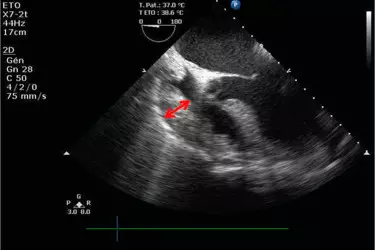

Echo also can pinpoint areas of heart muscle that aren't contracting well because of poor blood flow or injury from a previous heart attack. A type of echo called Doppler ultrasound shows how well blood flows through your heart's chambers and valves. A healthy heart must have an Ejection Fraction of 60% which means that each time your heart contracts it pumps 60% of the blood from the Left Ventricle to the Aorta. If the ejection fraction is low it means that heart will have to work more to pump the same amount of blood and this may slowly lead to heart failure. So getting an echocardiography regularly is a cheap and effective way of finding about the health of your heart.

Echoccardiography can detect many heart problems. Some might be minor and pose no risk to you. Others can be signs of serious heart disease or other heart conditions. An echocardiogram is key in determining the health of the heart muscle, especially after a heart attack. It can also reveal heart defects in unborn babies. If you’re diagnosed with a heart condition, your doctor will work with you to develop a treatment plan that works best for you.